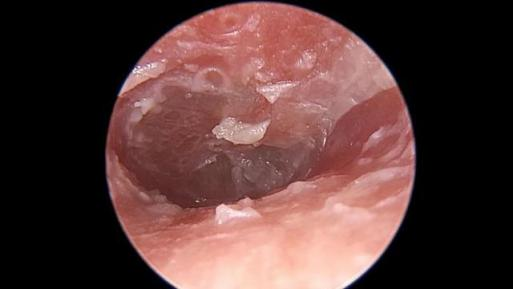

事故一: 医生诊断女孩为霉菌性外耳道炎,因为不确定菌种,还需要进行分泌物培养,再对症下药。 事故二: 杭州60岁一大爷也遇到了耳朵长毛的情况。章大爷前一天自己掏完耳朵,第二天耳朵就痛痒难忍,前来就医。 霉菌性外耳道炎和吴先生的脚气进耳朵是一个道理,都是真菌感染,只不过致病菌可能会不同。脚气的病菌多为红色毛癣菌、石膏样毛癣菌、絮状表皮癣菌、犬小孢子菌、石膏样小孢子菌、白色念珠菌......而耳朵的致病菌多为以曲霉菌、念珠菌、青霉菌及毛霉菌。 不过相同的是,这些菌都可能因为工具而带入耳朵,并在耳朵里落地生根...... 根据不同真菌种类,耳朵长出的“毛”颜色也会不一样。 曲霉菌、青霉菌感染,菌落的“毛”会是绿色的。 念珠菌、毛霉菌感染,“毛”会是白色的,程度轻的能看到一些霉丝和霉点,严重的可能会有一些脓性分泌物。 还有黑色的“毛”。不过这可能不是单一感染了某种真菌,还可能是:耳屎堵在耳朵里时间太长,让它在外耳道内潴留局部发生氧化了;陈年血痂被抠了出来;感染了黑色真菌后的团块;黑色素瘤之类的疾病(不过一般抠出来的会是黑色新生物,大多数伴有疼痛和出血)。 其实真菌进耳朵,在多数情况下都可以避免。 比如减少掏耳朵的次数。“耳屎”耵聍是保护着我们的耳朵的,它呈弱酸性的,有抑制真菌生长的作用,如果频繁掏耳朵,将耳道清理得过分干净,就会使耳道失去一层保护屏障。 用一次性采耳工具,减少交叉感染的可能。耳道也有着自己的微生物环境,当表皮葡萄球菌和棒状杆菌占多数时,耳道会更健康。如果霉菌进入耳道,菌落的平衡破坏,耳道就会真菌感染。 表皮葡萄球菌正常存在于人的皮肤、鼻腔及肠道中 棒状杆菌 如果实在觉得耳朵被“堵”住了,难受得不得不掏,又不敢自己掏,可以挂耳鼻喉科,让医生来一波专业操作! 02 硬核异物篇 玩具零件、泥土、木块金属块......总有些硬核异物在不断突破耳朵的感受。 事故三: 24岁的于先生掏因为耳朵掏不动而到医院检查,医生发现他的耳道里竟然有个算盘珠! 回溯起来,原来这颗算盘珠是他自己10岁的时候塞进耳朵的,因为当时怕被家长骂就没说而不了了之,于是这颗珠子就在于先生的耳朵里安安静静地躺了14年。 事故四: 重庆市民彭女士在给六岁的儿子豪豪掏耳朵时,发现他的耳朵里好像有异物,于是便把他送到医院检查。 医生在豪豪耳朵里取出了一棵植物种子,并且已经发芽! 医生表示,耳道里的温度是37度左右,再加上比较湿润,是适合种子生长、发芽的,这种情况如果再晚些就医,很可能会对孩子的听力造成损伤。 事故五: 以及这位心大患者,用金属硬物抠耳朵,但是金属却塞到耳道深处拿不出来了。 左方耳道亮光为金属异物,图片来自医脉通 耳道是用来传递声波的,有着一定的长度和宽度,大概长度2.5-3.5cm,粗0.7cm 左右,别看小小的几厘米,却有可能因为它弯曲的形状而藏住小东西! 成人的耳道走形略成“S”,先向前上弯曲,然后向后下,再向前下 不过为了避免进异物,耳朵也有着对策。耳道内的皮肤上分布着毛囊和耵聍腺,耵聍腺会分泌一定量的耳屎来粘附灰尘和进入的外物,耳朵里的小绒毛也会阻挡异物进入。 其实耳朵在一般情况下并不容易进入异物,如果进了东西,多数当时就会感到疼痛。 但因为每个人的外耳道长度不一样,进了东西后感受也可能不同,有的人会有异物感、阻塞感、听力改变等症状,也有的人当时感觉不到异常。 所以,蝌蚪君叮嘱一句,如遇耳朵进了异物又拿不出来,一定要及时去医院,免得自己的胡乱操作损伤了听力! 03 恐怖爬虫篇 事故六: 大连市中心医院接诊了一位60多岁的男性老人,他在前一晚睡觉时感觉耳朵里面不舒服,但没在意,第二天醒来耳朵里就像敲鼓一样。 医生检查后发现老人的耳道被一层白雾一样的絮状物封闭了,像网一样的这层絮状物背后,一个类似虫子的活物在不断地动。 原来是进入耳道的蜘蛛已经在里面结了网! 医生用专用的耳道清洗器向老人的耳道内注水清洗,一只绿豆大小的蜘蛛才被冲洗了出来。 想要避免自己碰到样的恐怖情况,最有效的办法就是保持家中卫生干净,多做蚊虫的消杀。尤其在家里经常见到小飞虫、瓢虫、蚰蜒(俗称草鞋底)、小蟑螂,需要格外保持警惕,这些虫子尤其喜欢温暖潮湿的人类耳朵! 但是如果真的遭遇虫子进耳道,千万别用土办法解决,比如滴香油、食用油、醋,还有用手电筒照亮,吸引虫子…… 这样不仅不科学,还容易造成耳道感染,让耳道内的情况更加复杂,给治疗带来难度。 04 悲伤事故篇 虽然“做完手术落下了纱布”这种传说级的事故,在普通外科手术上鲜有发生(每一场外科手术都会清点医疗用品数量),但在耳朵手术里发生的概率的确会比普通手术更高。 耳科病人做完手术后,进行术后调理和康复时一般会给病人耳部覆盖上无菌纱布,用来包扎敷料、消毒或保护手术部位,这也给将纱布、棉花误留创造了机会。 不过随着医疗水平的提高,这种小概率事件以及极少发生了,大家不必过度担忧。 05 避免耳朵生长奇怪的东西 要养成正确的卫生习惯 很多人比较享受掏耳朵的过程,前往采耳店、足疗店、按摩店掏耳朵,觉得掏完身心轻松,非常解压。 但是顾客们都同用一套工具,万一遇到消毒不到位的情况,采耳就变成了“真菌杂烩”,如同足疗传染脚气,采耳也容易将上一个客人的“耳气”带回家。 当然,也别矫枉过正,用耳毛来挡住异物(一般人做不到)。 世界上最长的耳毛50公分,其实他是患了“传男不传女”的人类外耳道多毛症 如果真的感觉自己的耳屎太多,有种堵了东西的感觉,甚至了影响听力,在医学上这种情况叫做耵聍栓塞。可以前往正规医院耳鼻喉科挂号,医生将会用药水、无影灯、内窥镜等工具进行安全可靠的“掏耳屎”(据说掏过的人在看到“成果”时都非常的爽),蝌蚪君也想尝试一二! 你耳朵曾经进过东西吗?你有听闻过身边朋友耳朵进过奇葩东西吗?他们都是怎样处理的呢?快在评论处告诉蝌蚪君吧! 审核专家:袁先道,首都医科大学北京安贞医院耳鼻喉科副主任医师,医学博士。 来源:蝌蚪五线谱